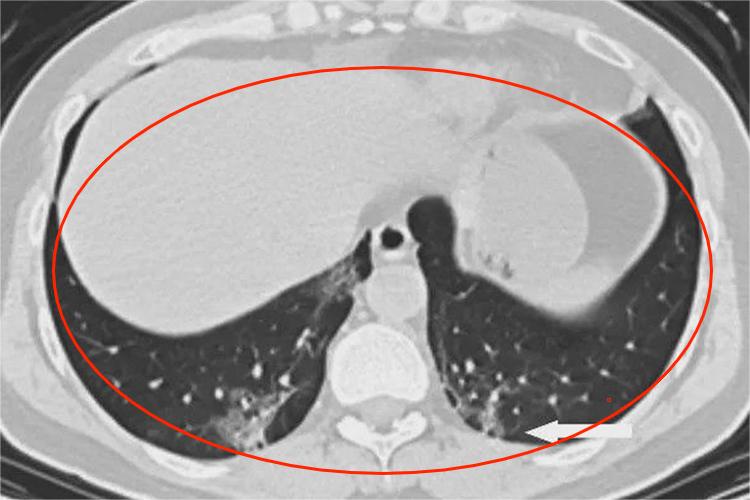

- 一般来说,肺上的增殖灶多为良性病变。例如曾经患过肺结核,经过治疗或者自身免疫作用,病情得到控制和好转,在肺部可能会留下一些增殖性的病灶,表现为肺部的钙化点或纤维条索影。

- 这些增殖灶通常比较稳定,不会迅速增大或发生形态上的明显变化。而且,大多数情况下,它们不会引起明显的临床症状,对肺功能的影响也较小。

- 对于一些特殊情况,仍需要密切关注。如果增殖灶的形态不规则、边缘不清晰、短期内迅速增大,或者伴有咳嗽、咯血、胸痛、消瘦等症状,就需要警惕是否存在恶变的可能,比如肺癌。